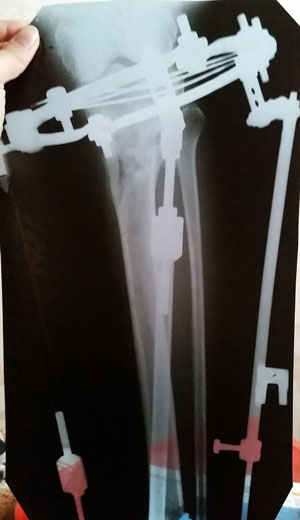

рентген в 90 дней с момента операции.

Ураа аЗдравствуйте, Ласка! По рентгену всё идёт хорошо, регенерат хороший, всё по плану. Через месяц будем готовиться к снятию аппаратов! (предварительно сделав рентген и выслав нам).